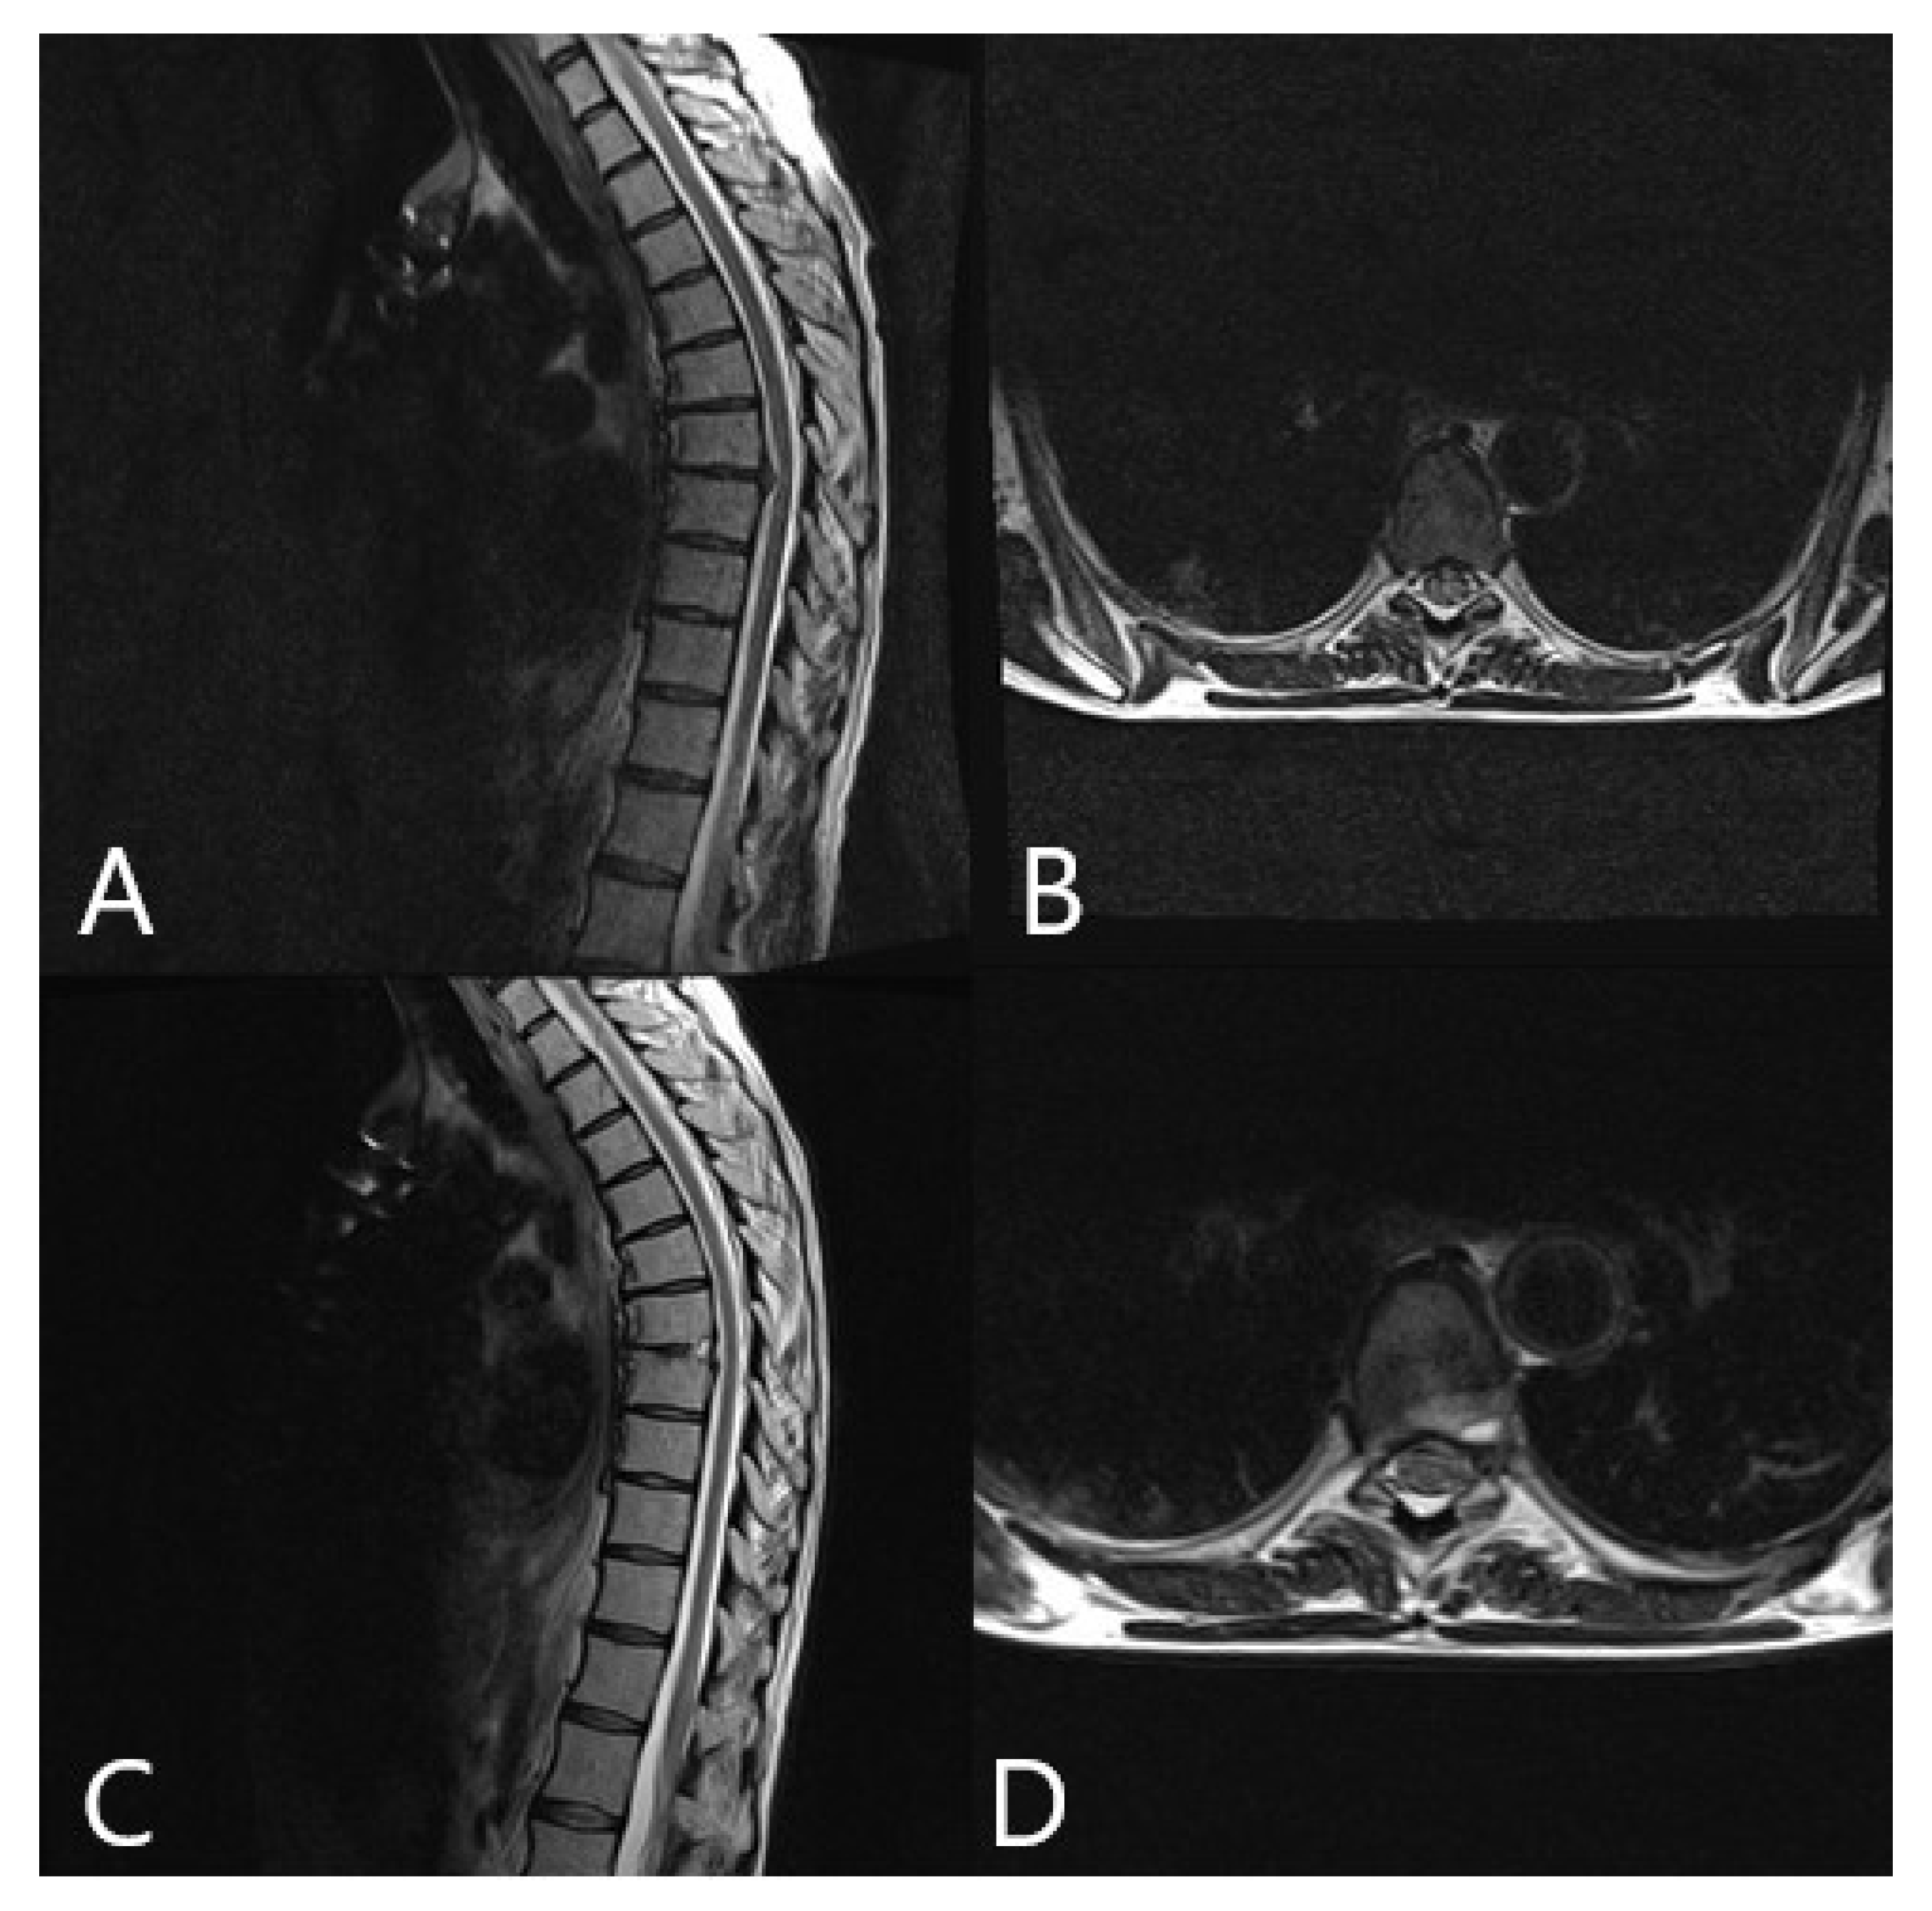

| 3 | 66 | F | Calcified herniated disc Th 9/10 | Ataxia Paraparesis 4/5 | Left lateral retropleural approach, sequestrectomy of the herniated disc | None | Improvement of ataxia following surgery |

| 4 | 19 | F | Giant aneurysmatic bone cyst Th 8/9 | Back pain | 1. Hemilaminectomy T8/9, Resection of the thoracic nerve origin 2. Tumor resection via left retropleural approach, Resection of 7/8 Rib with reconstruction of the thoracic wall | No | No pain, no deficits, and no recurrence at follow up |

| 8 | M | 51 | Herniated disc T8/9 with myelopathy | Back pain, paraparesis 3/5, urinary incontinence | 1. Partial resection of the herniated disc via posterior approach with right costotransversectomy 2. Resection of the remaining disc via left retropleural approach 3. Stabilization T8-9 | No | No pain and no deficits following surgery |

| 9 | F | 52 | L2 Neurinoma | Back and hip pain | Resection of neurinoma via left retroperitoneal approach | No | No pain, no deficits, and no tumor recurrence at follow up |

| 10 | F | 63 | Herniated disc T 7/8 with myelopathy | Worsening of back pain due to chronic pain syndrome following multiple spine surgeries, ataxia | Left lateral retropleural approach, sequestrectomy of the herniated disc | No | Chronic pain syndrome with moderate improvement, no ataxia, no deficits at follow up |

| 14 | F | 48 | Schwannoma Th11/12 | Back pain | 1. Resection of T12 nerve root via dorsal approach. 2. Left lateral transpleural approach, resection of the tumor | None | Improvement of back pain following surgery |

| 15 | F | 46 | Calcified herniated disc Th 7/8 | Back, pain, paraparesis | Left lateral retropleural approach, constotransversectomy, total resection of the herniated disc | None | Improvement of back pain and paraparesis following surgery |

| 16 | M | 38 | Calcified herniated disc Th 9/10 | Back pain, paraparesis | Left lateral retropleural approach, costotransversectomy, subtotal resection of the herniated disc | None | Improvement of back pain and paraparesis following surgery |